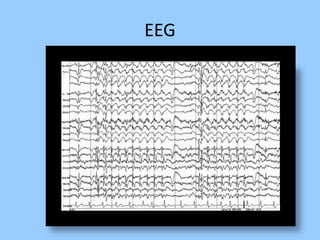

1. The document discusses EEG patterns and findings in various neurological conditions seen in children. It includes descriptions of normal EEG findings as well as abnormal patterns seen in conditions like absence seizures, West syndrome, benign childhood epilepsy with centrotemporal spikes, Lennox-Gastaut syndrome, non-convulsive status epilepticus, subacute sclerosing panencephalitis, and herpes encephalitis.

2. Case studies are presented with clinical histories and EEG findings to illustrate different pathologies. Treatment options are also mentioned for many of the conditions.